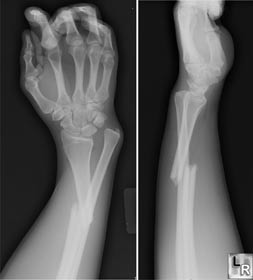

每逢大雪过后,由于路面湿滑,部分路面结冰,医院里因摔伤造成骨折及外伤的患者会增多。搜狐健康提醒您:雪后路滑,注意慢行。同时还建议您掌握一些摔伤(骨折)后的急救处理方法。

身体的各个部位都可能发生骨折。发生骨折后,局部有疼痛和压痛,肿胀、畸形和功能丧失,骨折处有时可触到骨磨擦音,依靠X光片,一般可以确诊。

行人要走人行道,不要在机动车道上行走,防止被侧滑的车碰到; 走路速度不要太快,最好穿防滑鞋或旅游鞋。 如果突然摔倒,尽量别用手腕去支撑地面,因为这种摔倒姿势最容易造成手臂骨折。 万一发生骨折,切不可乱揉乱动,应用围巾、书本等工具固定好骨折部位,请求他人帮助,到附近医院治疗。